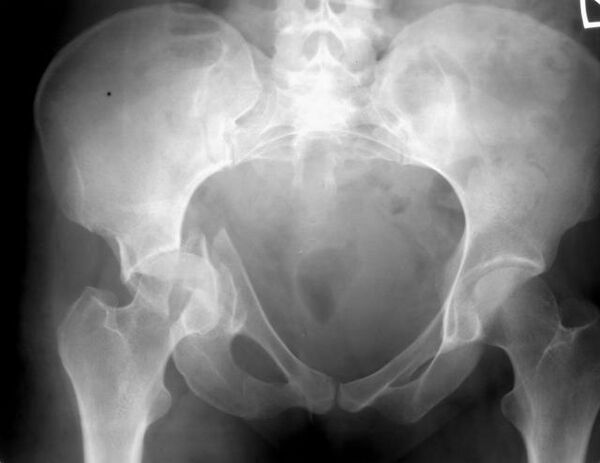

Тазовая кость (лат. os coxae) — это обозначение для парной кости правой и левой, которые относятся к поясу нижних конечностей, а вместе с крестцом и копчиком образуют таз. Используется также название безымянные кости. Каждая из тазовых костей в свою очередь образована тремя составляющими: подвздошной костью, седалищной костью и лобковой костью, которые соединяются посредством хряща в области вертлужной впадины, служащей местом соединения тазовой кости с бедренной. В возрасте 14-16 лет эти три кости срастаются, образуя единую тазовую кость.

Подвздошная кость (лат. os ilium) составляет ближайшую к позвоночнику часть пояса задних конечностей или таза, сочленяющуюся с крестцовыми позвонками. Она ясно выражена уже у амфибий. У человека она сочленяется крестцовой костью, являющейся результатом слияния 5 позвонков, и в области вертлужной впадины, служащей для помещения головки бедра, срастается с двумя другими тазовыми костями: седалищной и лобковой. Верхний край подвздошной кости человека закруглён, передний и задний образуют по два выступа (лат. spinae anterior superior, ant. inferior, posterior superior, post. inferior), а на своей внутренней и наружной поверхности она имеет изогнутое линейное возвышение (linea arcuata inferior et exterior).

Седалищная кость (лат. os ischii) — одна из костей пояса задних или нижних конечностей, иначе таза. Она ясно выражена уже у амфибий. У человека она состоит из следующих частей: тело, которое соединяется сверху с подвздошной костью, а спереди с лобковой горизонтальной ветвью и вместе с этими костями образует тазовую кость (os coxae). В месте соединения этих костей находится вертлужная впадина (acetabulum) для приёма бедренной головки. От тела вниз на задней части отходит нисходящая ветвь (ramus descendens), образующая на нижнезаднем углу седалищный бугор (Tuberculum ossis ischii) и продолжающаяся вперёд и вверх в виде восходящей ветви (ramus ascendens). Последняя с нисходящей ветвью лобковой кости, и таким образом между телом седалищной кости, её обеими ветвями и обеими ветвями лобковой образуется овальной формы отверстие (foramen obturatum sivo ovale).

Лобковая кость (лат. os pubis) — одна из трёх костей, образующих при сращении тазовую кость. Состоит из тела и двух ветвей. Ветви и тело лобковой кости образуют запирательное отверстие (foramen obturatoris), закрытое запирательной мембраной. Две лобковые кости, срастаясь, образуют переднюю стенку таза.